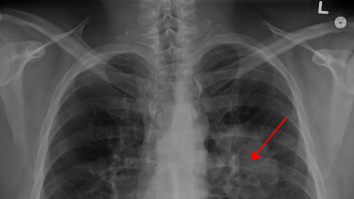

În Marea Britanie, peste o mie de persoane dezvoltă cancer pulmonar din cauza poluării

Tot mai mulți nefumători fac cancer pulmonar. Ce spune OMS

STUDIU. Care ar putea fi cauza cancerului pulmonar? Cercetătorii spun că 15-20% din cazuri apar la persoanele care nu au fumat niciodată

Oamenii de știință au descoperit modul în care poluarea aerului poate declanșa cancerul pulmonar la cei care nu au fumat niciodată